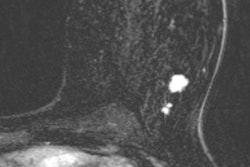

The approach features a form of diffusion-weighted MRI (DWI-MRI) known as diffusion kurtosis imaging, which analyzes the distribution of water to evaluate breast tissue structures at a microscopic level. A software algorithm based on a kurtosis radiomics model then extracts imaging data to accurately characterize the lesions (Radiology, February 20, 2018).

"[The] model ... reduces false-positive results by 70% in lesions classified as BI-RADS 4 or 5 at screening mammography while retaining sensitivity greater than 98%," wrote lead author Dr. Sebastian Bickelhaupt, from the German Cancer Research Center in Heidelberg, and colleagues. "Since malignant lesions disrupt the tissue structures at this level, diffusion kurtosis might serve as a relevant marker of changes."

"A radiomics breast cancer model based on DWI with adapted kurtosis fitting allowed for improved differentiation between malignant and benign breast lesions in both training and independent test datasets acquired by using MR imaging machines from different vendors at different institutions," Bickelhaupt and colleagues wrote.